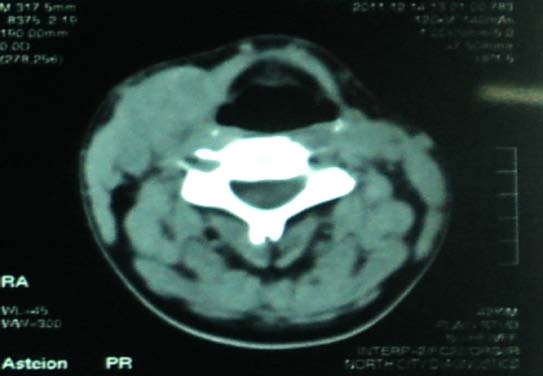

When the presence of cystic necrosis and calcifications within the lymph node are observed; then the specificity is almost 100% in those patients with PTC. Such a picture is absent in normal or reactive lymph nodes. [10,13] CT and MRI (magnetic resonance imaging) are indispensible tools in evaluating neck masses. Definitive features of central necrosis, thickened walls, intracystic elements, calcifications, greater peripheral uptake observed in CT scans with contrast, [14] are suggestive of a metastatic thyroid lesion with 100% sensitivity and 90% specificity as compared to sonography with 80% specificity [11,15] as observed in our case.